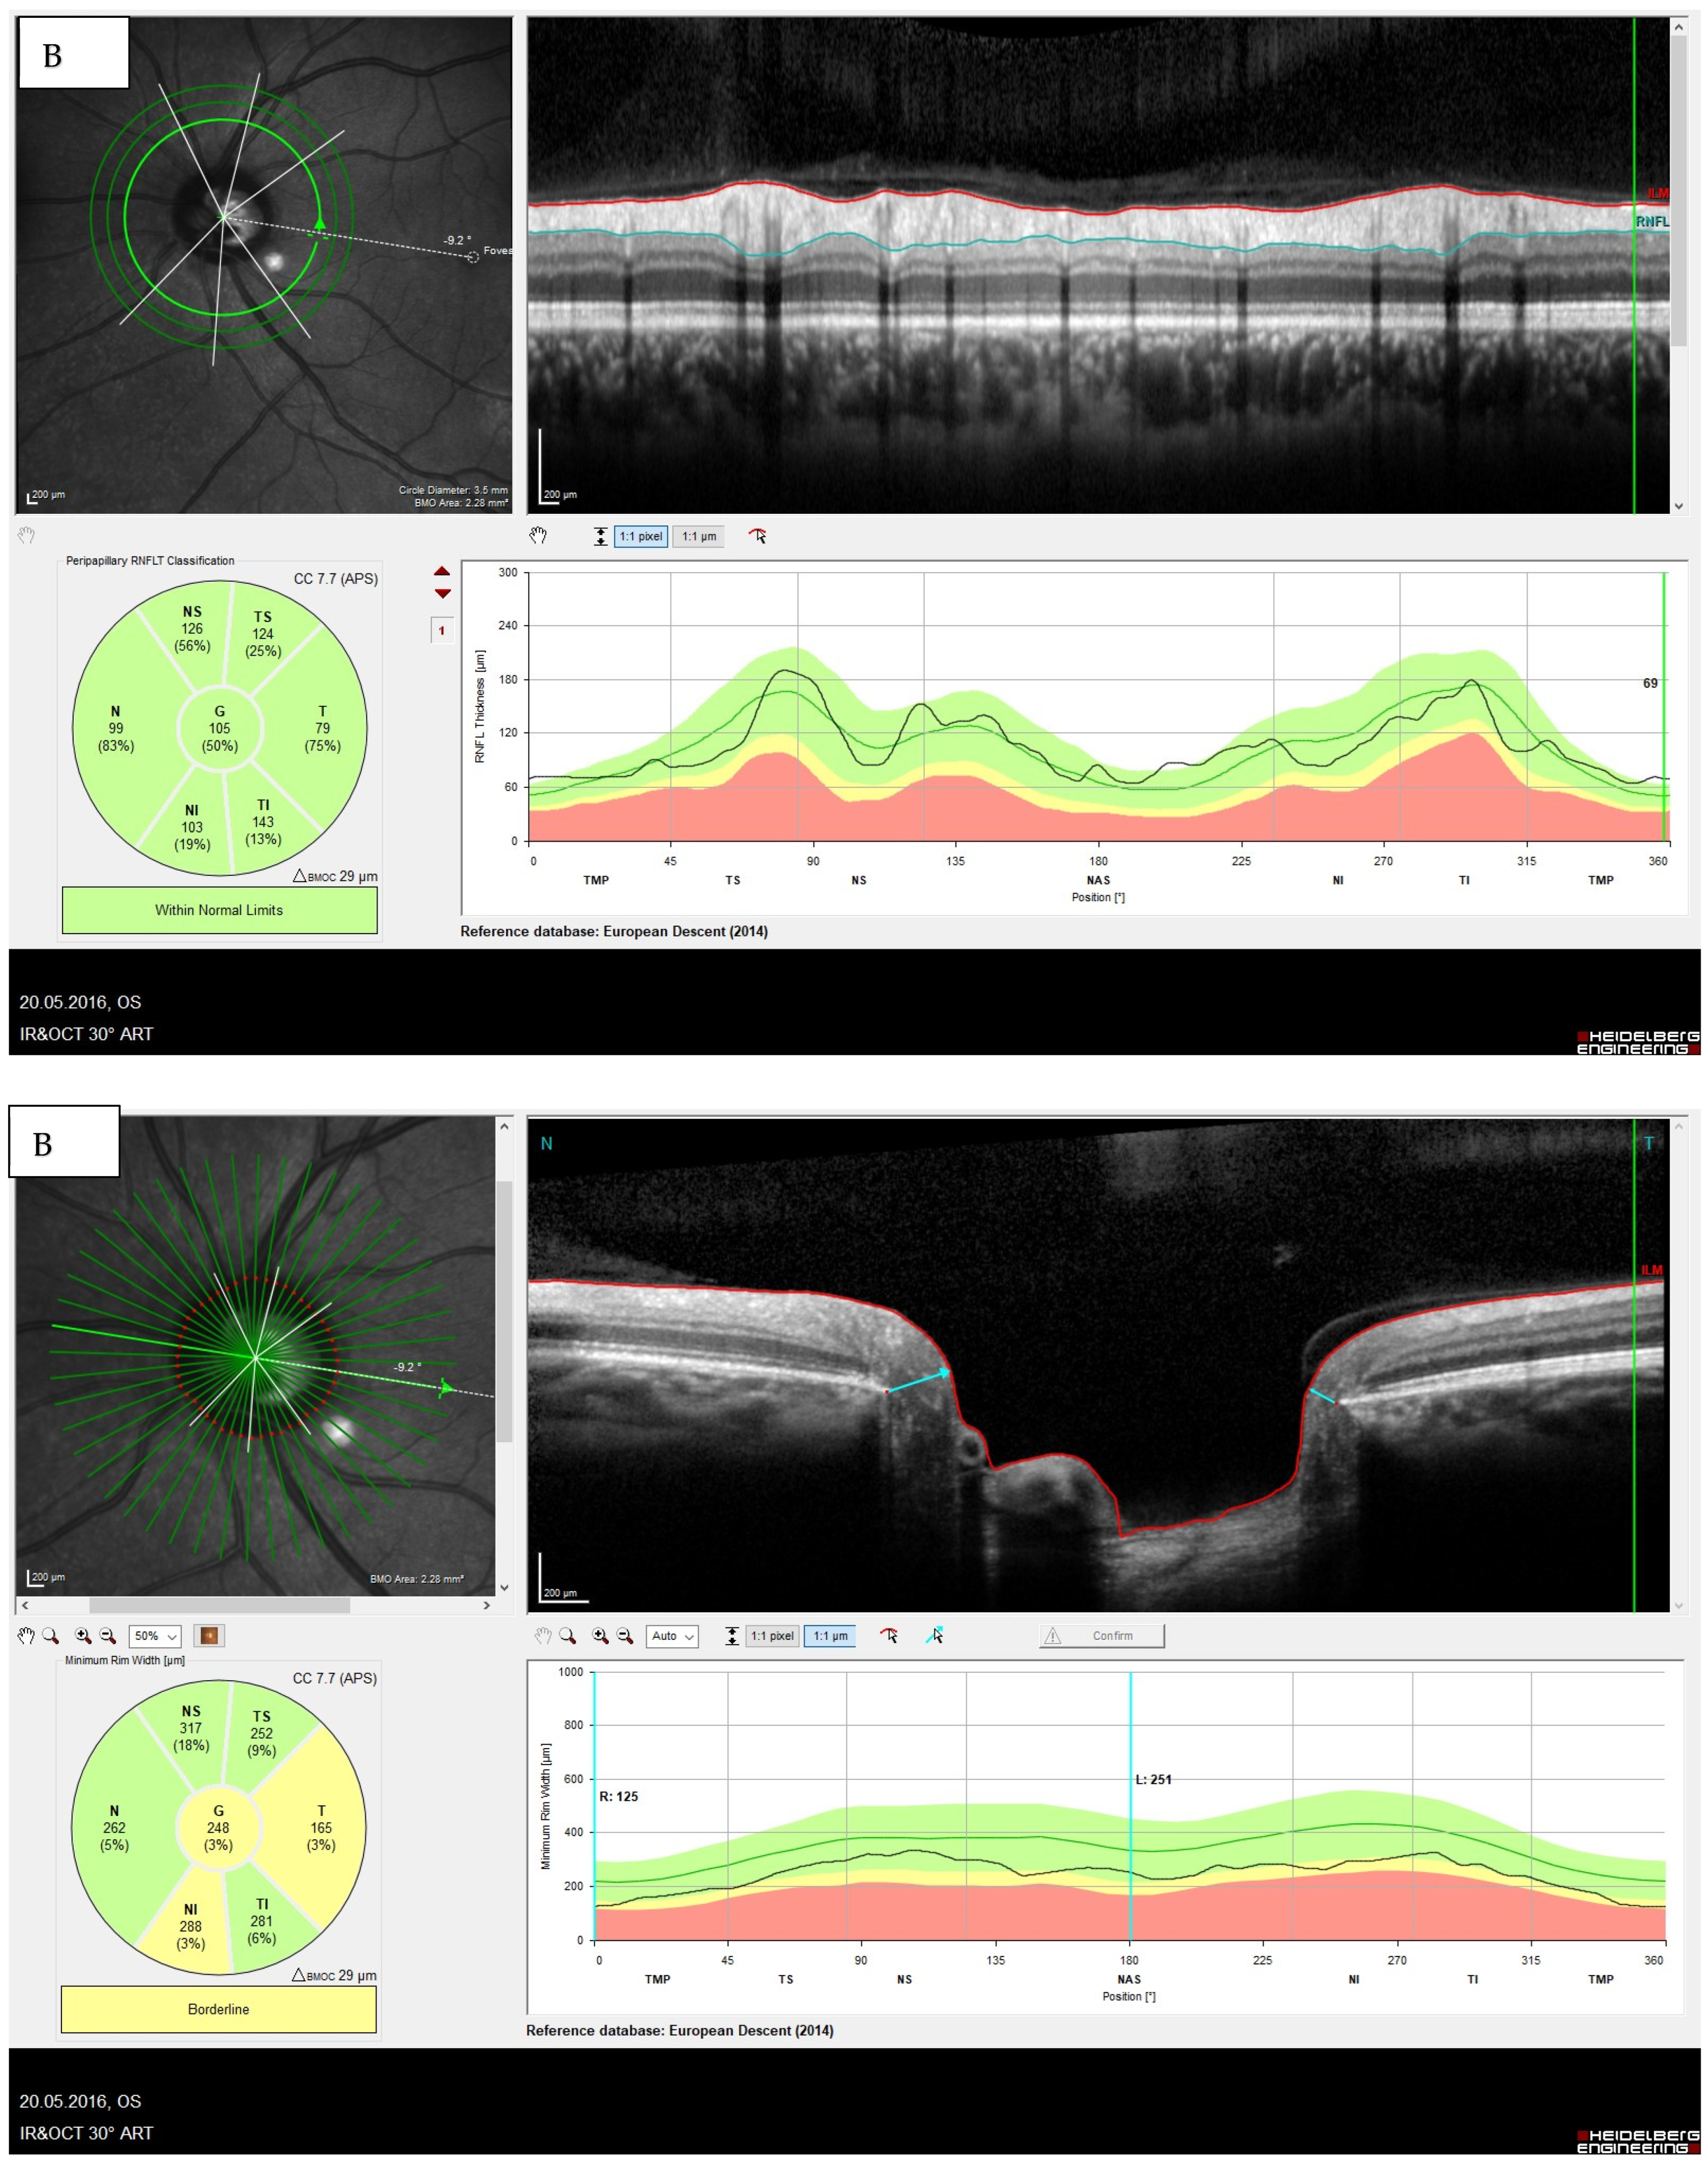

The Minimum Rim Width (MRW)

- Influence of the optic disc size on the MRW:

- Influence of refraction on MRW